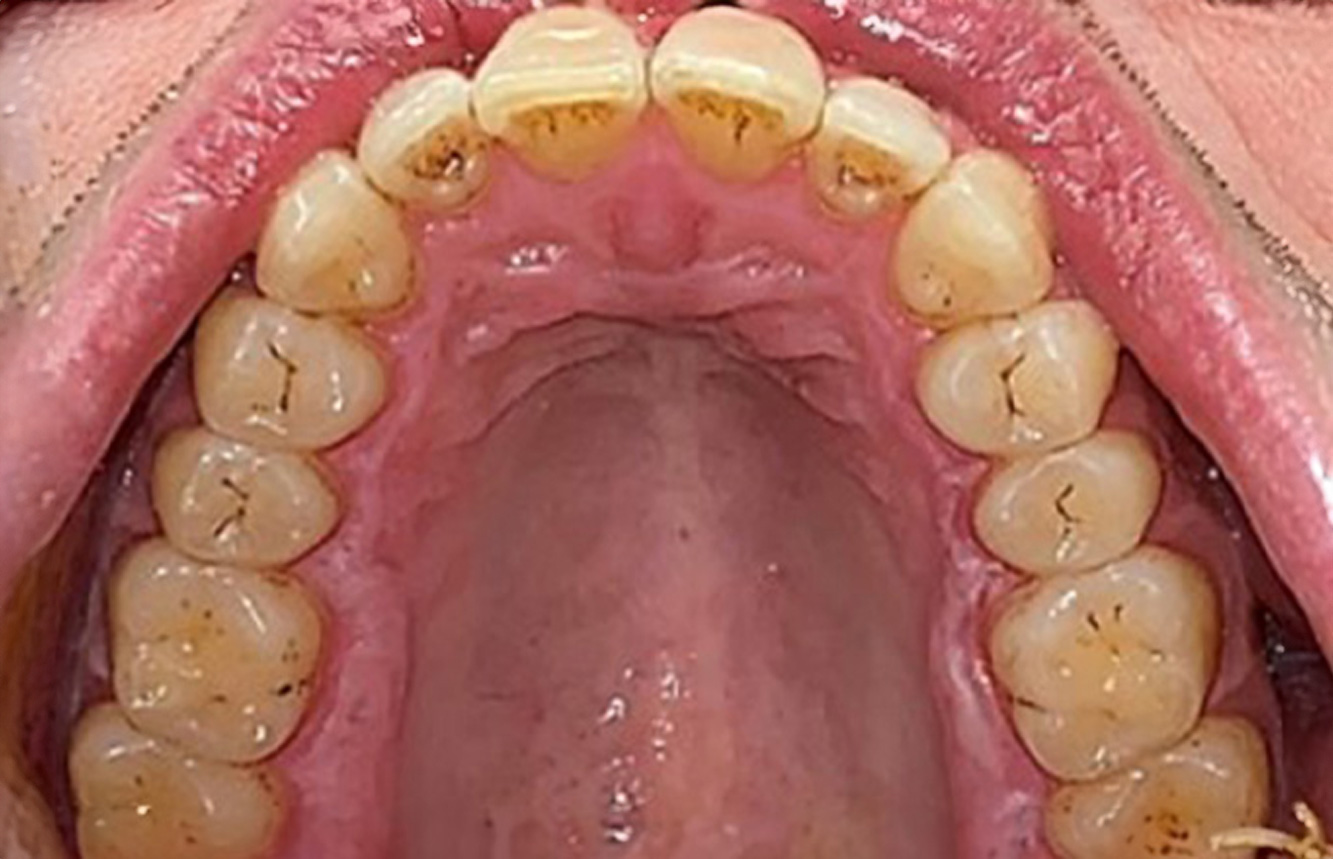

Pacient transplantat cu proliferări gingivale

Un pacient în vârstă de 71 de ani, cu transplant de rinichi și istoric de hipertonie (hipertensiune arterială) se prezintă în cabinet. Din cauza istoricului său medical, este necesară o medicație pe termen lung cu ciclosporină, pentru a suprima sistemul imunitar, precum și amlodipină pentru a reduce tensiunea arterială. Pacientul raportează, de asemenea, gingii sensibile și sângerânde. Din punct de vedere al sănătății orale, pacientul are lucrări dentare, o edentație de opt dinți, creștere gingivală pronunțată și parodontoză de gradul B, stadiul II, cu pungi active și carii radiculare inițiale la dintele 22. Evaluarea riscului de carie determină un risc moderat de carie (API 60). Se pot stabili următoarele recomandări de tratament pentru ședința de profilaxie. mai multe